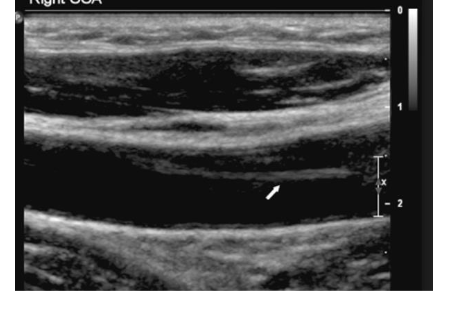

Where does atherosclerosis most commonly form at, what makes it form

-usually at the carotid bifurcation, (any bifurcation), aorta iliac system, and the CFA

formed as a result of a deposition of material in the arterial walls between the intima and media, its an accumulation of lipid containing material, smooth muscle cells, fibrin and platelets,